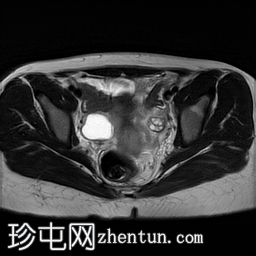

轴向

T2

子宫体相对较小,发育良好。宫颈发育不全。

阴道整体不显影,远端可见一层细小的纤维组织,在轴向和矢状面T2加权序列上最为明显。

随后,子宫内膜和宫颈腔扩张,出现混合液体/血液降解信号(积血)。它诱发中至高T1信号,伴有依赖性低信号碎片,无病理性强化。

周围轻度盆腔积液,盆腔及附件脂肪平面模糊,信号相似,增强后强化明显。这些发现提示可能有渗漏液/血液积聚,并伴有腹膜反应。

右侧附件卵巢功能性囊肿。